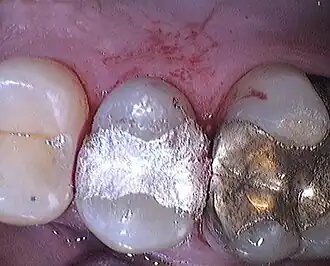

Definitieve vullingen kunnen rechtstreeks aangemaakt worden en in de mond geplaatst worden. Vroeger was het enig materiaal bladgoud. Maar nu worden amalgaam en composiet gebruikt. Amalgaam wordt aangevochten omwille van de kwik die het bevat. Biologische tandartsen gebruiken nooit amalgaam.

Naast deze rechtstreekse methoden bestaan er ook onrechtstreekse methoden waarbij de tandarts na het uitcuretteren van de cariës en het beslijpen van de tand, een afdruk neemt van de mond waarna een tandtechnieker de restauratie (inlay of onlay) in goud, porselein of kunsthars zal maken die de tandarts uiteindelijk in een volgende zitting in de tand zal cementeren of kleven.